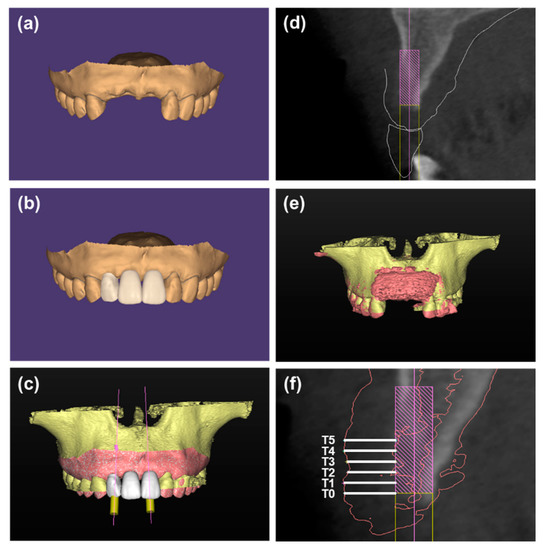

- Received one of the following GBR procedures: particulate bone substitute +CM (Group 1), particulate bone substitute + CM + healing caps (Group 2), sticky bone + CM + pins (Group 3), or sticky bone + CM + pins + surgical template (Group 4).

2.3. CBCT Analysis

- The use of surgical templates contributed to an appropriate contour of bone grafts after wound closure.